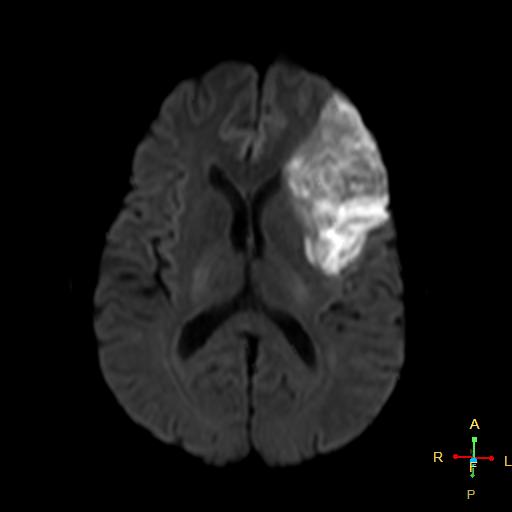

画像提供:Radiopaedia

Q1.画像から予測できる脳卒中の病態は何でしょうか

Q2.画像から考えられる離床のリスクは何でしょうか

Q1.境界明瞭な脳梗塞であり、心原性脳塞栓症であると考えられる。

Q2.離床は心機能と残留する心内血栓による再発に留意して進める必要がある。